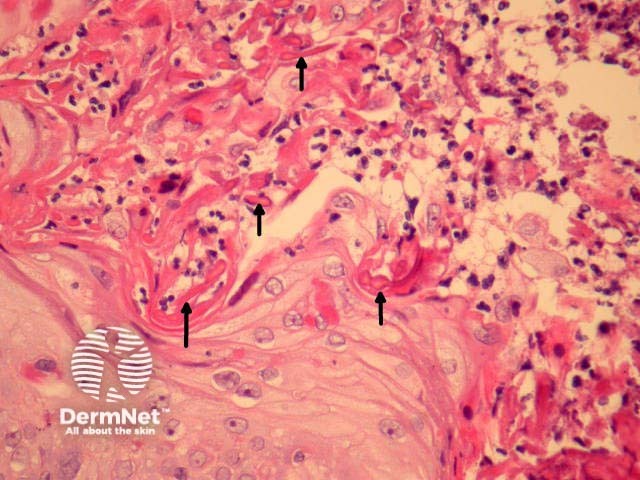

Sections show a suppurative folliculitis on low power examination (figure 1). Higher power examination shows debris and acute inflammation within a distorted follicle (figures 2-4). Collagen fibres and elastic fibres can be seen penetrating into the follicular space (figures 3-4, arrows highlight extruded fibres). There is frequently degeneration of dermal connective tissue adjacent to the involved follicle.

The extruded fibres can be demonstrated with an elastic stain (e.g. EVG) and collagen stain (e.g. trichrome)